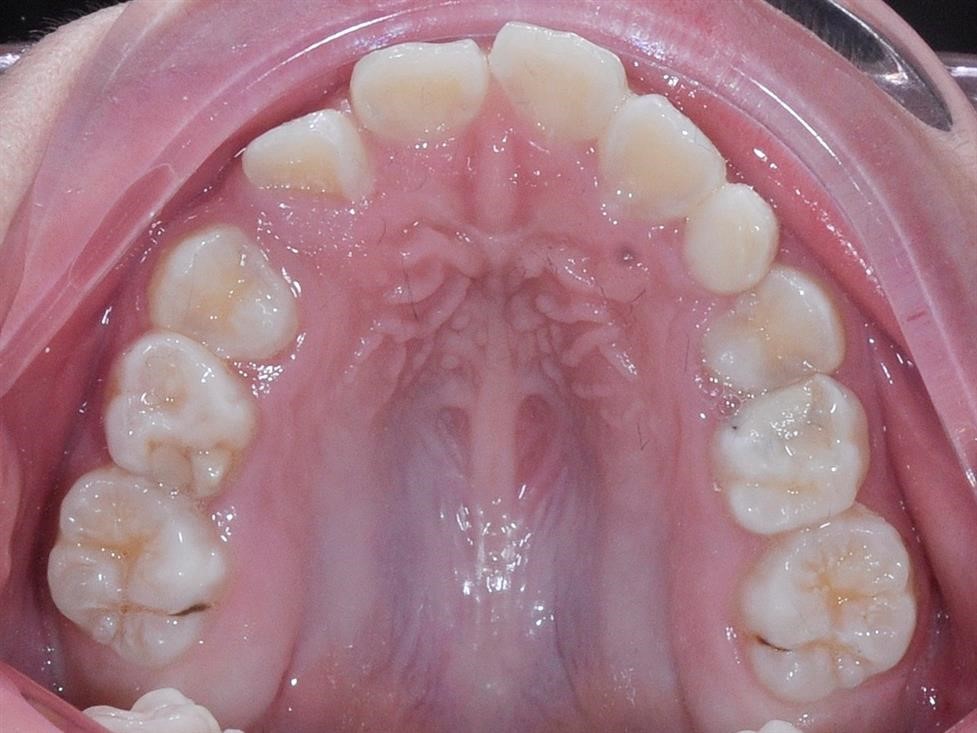

Đây là thời kỳ thích hợp nhất để hướng dẫn cắn khớp và ngăn chặn sai khớp cắn. Nha sĩ sẽ có thách thức lớn nhất cũng như cơ hội tốt nhất để tiến hành điều trị có hiệu quả. Lí do điều trị: a) Loại bỏ các cản trở sự phát triển bình thường của bộ răng. b) Điều trị sai khớp cắn ở bộ răng vĩnh viễn không thể hiệu quả hơn. Điều trị tập trung vào việc hướng dẫn tăng trưởng, ngăn ngừa sự phát triển của sai khớp cắn và lọai bỏ các dấu hiệu đầu tiên mà có thể làm cho sai khớp cắn trở nên trầm trọng hơn ở giai đoạn răng vĩnh viễn. Các trường hợp cần điều trị: a) Sự mất răng sữa gây nguy cơ thiếu khoảng trên cung hàm. b) Sự đóng khoảng do sự mất sớm các răng sữa. Khoảng bị mất trên cung hàm cần phải được hồi phục.

c) Răng mọc sai vị trí gây cản trở phát triển chức năng cắn khớp bình thường, gây rối loạn mọc răng hoặc há ngậm miệng, hoặc gây ảnh hưởng xấu đến sức khỏe răng miệng. d) Răng thừa có thể là nguyên nhân gây sai khớp cắn e) Khớp cắn chéo ở răng vĩnh viễn

g) Thiếu răng nếu đóng khoảng sớm có thể tránh làm răng giả h) Khe thưa giữa các răng cửa giữa hàm trên có điều trị chỉnh nha i) Khớp cắn bình thường nhưng có vẩu xương hàm trên quá mức j) Khớp cắn loại II type chức năng k) Khớp cắn loại II do răng

l) Khớp cắn loại II do xương, đặc biệt trong trường hợp điều trị hai pha được chỉ định m) Thiếu khoảng nhìn thấy rõ Các trường hợp có thể điều trị: các điều kiện có thể điều trị ở giai đoạn hàm răng hỗn hợp là: a) Sai khớp cắn loại II do xương, đặc biệt trong trường hợp điều trị hai pha được chỉ định b) Sai khớp cắn loại III mà điều trị sớm có khả thi c) Tất cả các sai khớp cắn mà răng quá to, nếu có chỉ định nhổ răng hướng dẫn thì cần điều trị sớm từ lúc giai đoạn răng hỗn hợp. d) Mất hài hòa nền xương 3. Kế hoạch điều trị ở hàm răng vĩnh viễn